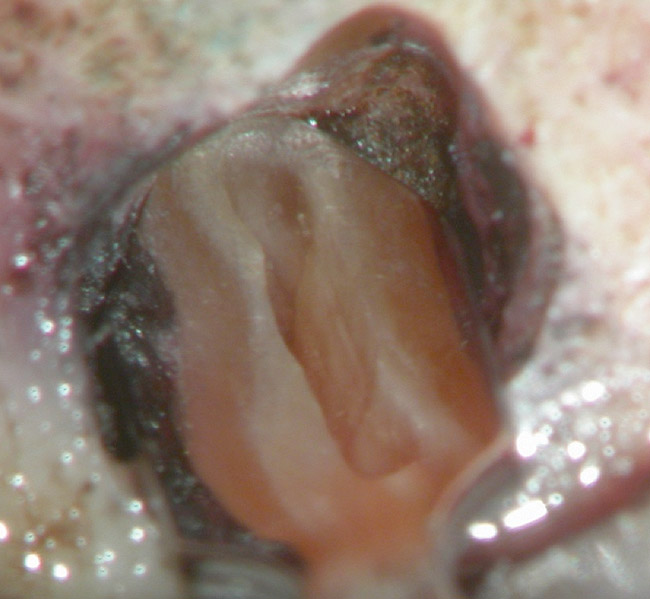

Figure 4b  The patient was asymptomatic, and periodontal probing depths were within normal limits; however, a new crown restoration was planned. Nonsurgical endodontic re-treatment was initiated. The intracoronal picture shows the previously treated 4 canals with infected gutta-percha filling.

Figure 4b

Figure 4c  Under high magnification, a furcation canal (Figure 4C) and a third distal canal (Figure 4D) were located.

Figure 4c